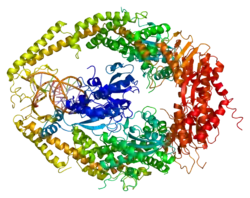

DNA mismatch repair protein Msh2 also known as MutS homolog 2 or MSH2 is a protein that in humans is encoded by the MSH2 gene, which is located on chromosome 2. MSH2 is a tumor suppressor gene and more specifically a caretaker gene that codes for a DNA mismatch repair (MMR) protein, MSH2, which forms a heterodimer with MSH6 to make the human MutSα mismatch repair complex. It also dimerizes with MSH3 to form the MutSβ DNA repair complex. MSH2 is involved in many different forms of DNA repair, including transcription-coupled repair,[5] homologous recombination,[6] and base excision repair.[7]

In eukaryotes from yeast to humans, MSH2 dimerizes with MSH6 to form the MutSα complex,[13] which is involved in base mismatch repair and short insertion/deletion loops.[14] MSH2 heterodimerization stabilizes MSH6, which is not stable because of its N-terminal disordered domain. Conversely, MSH2 does not have a nuclear localization sequence (NLS), so it is believed that MSH2 and MSH6 dimerize in the cytoplasm and then are imported into the nucleus together.[15] In the MutSα dimer, MSH6 interacts with the DNA for mismatch recognition while MSH2 provides the stability that MSH6 requires. MSH2 can be imported into the nucleus without dimerizing to MSH6, in this case, MSH2 is probably dimerized to MSH3 to form MutSβ.[16] MSH2 has two interacting domains with MSH6 in the MutSα heterodimer, a DNA interacting domain, and an ATPase domain.[17]

The MutSα dimer scans double stranded DNA in the nucleus, looking for mismatched bases. When the complex finds one, it repairs the mutation in an ATP dependent manner. The MSH2 domain of MutSα prefers ADP to ATP, with the MSH6 domain preferring the opposite. Studies have indicated that MutSα only scans DNA with the MSH2 domain harboring ADP, while the MSH6 domain can contain either ADP or ATP.[18] MutSα then associates with MLH1 to repair the damaged DNA.

MutSβ is formed when MSH2 complexes with MSH3 instead of MSH6. This dimer repairs longer insertion/deletion loops than MutSα.[19] Because of the nature of the mutations that this complex repairs, this is probably the state of MSH2 that causes the microsatellite instability phenotype. Large DNA insertions and deletions intrinsically bend the DNA double helix. The MSH2/MSH3 dimer can recognize this topology and initiate repair. The mechanism by which it recognizes mutations is different as well, because it separates the two DNA strands, which MutSα does not.[20]